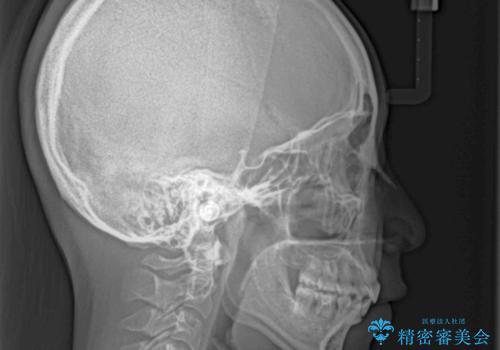

上顎抜歯のみでは奥歯の咬み合わせを改善することが困難であったため、途中で下顎小臼歯も抜歯をしました。

抜歯のタイミングが遅れると治療期間が長期化するため、速やかに抜歯の判断をし、2年強の期間で治療を終えることができました。